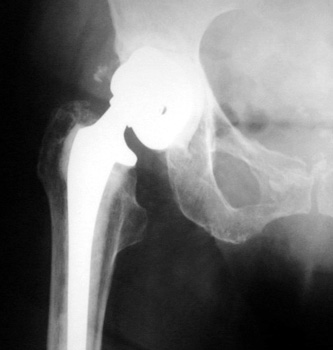

SUBSIDENCE - loose femoral prosthesis with interface widening,

osteolysis Gruen zone 6, cement fracture left femoral component

and osteolysis, with femoral component in valgus.